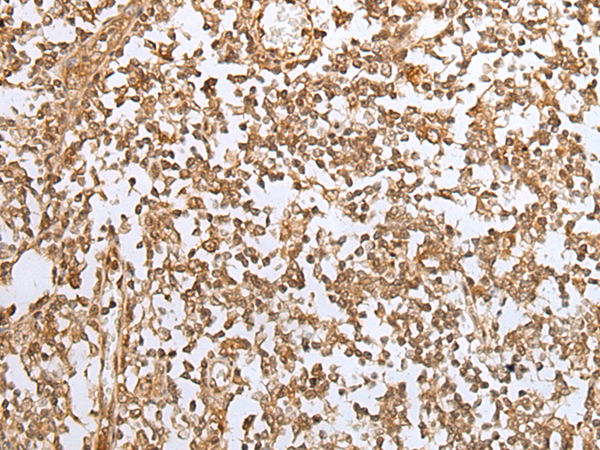

IHC positive control: |

Human gastric cancer and human tonsil |